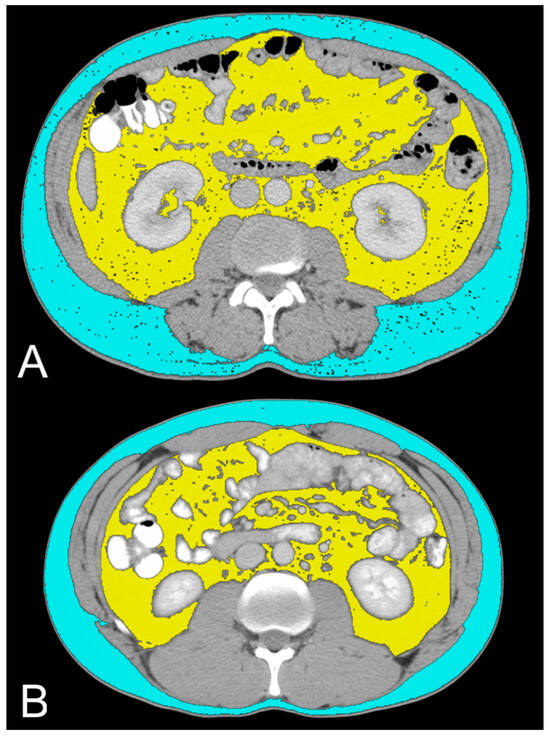

2.3. Lipid Metabolism Imaging Features

| VAT (cm2) | 213 (105, 299) | 196 (107, 245) | 0.6 |

| SAT (cm2) | 187 (141, 278) | 195 (148, 274) | 0.9 |

| TAT (cm2) | 430 (274, 530) | 381 (288, 506) | 0.6 |

| VAT (cm2) | 273 (225, 343) | 159 (95, 240) | 0.003 |

| SAT (cm2) | 226 (159, 419) | 158 (112, 228) | 0.045 |

| TAT (cm2) | 486 (423, 733) | 333 (200, 442) | 0.004 |